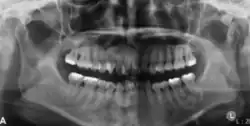

In its early stages, central ossifying fibroma (COF) appears as a small, well-defined radiolucent lesion due to its fibrous tissue content. Differential diagnoses at this stage include periapical pathology, central giant cell granuloma, and ameloblastoma.[22][23] As the lesion matures, it exhibits a mixed radiolucent-radiopaque appearance due to progressive calcification.[22] At this stage, it should be differentiated from other mixed jaw lesions such as fibrous dysplasia, calcifying epithelial odontogenic tumour, adenomatoid odontogenic tumour, and condensing osteitis.[22] In its mature form, COF may appear predominantly radiopaque, resembling lesions like odontomas, osteoblastomas, or osteosarcomas radiographically.

COF typically presents with well-defined, smooth, and often corticated borders. As a central lesion, it originates within the medullary bone and expands concentrically in all directions.[24] With growth, it may cause tooth displacement, root resorption, inferior displacement of the mandibular canal, and loss or alteration of the lamina dura of adjacent teeth.[25]

In conclusion, COF most commonly occurs in the mandible and expands from a central epicenter. Radiographically, it presents as a well-defined mixed-density lesion,[26] and Cone Beam CT (CBCT) plays a crucial role in its accurate diagnosis and assessment.